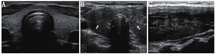

超声检查可以明确甲状腺大小、血供,发现甲状腺结节的位置、大小、数目和特征。大多数GD患者的甲状腺超声表现为弥漫性肿大且呈低回声,这主要是由于甲状腺内血流量增加、细胞密度增加、胶质含量减少及不同程度的淋巴细胞浸润(图1)。彩色多普勒超声中甲状腺血供丰富(与甲亢严重程度相关) (图2),可借此帮助鉴别GD和甲状腺毒症的其他原因,如破坏性甲状腺炎、外源性甲状腺素摄入过多(人为甲状腺毒症),这些改变甲状腺血供一般不增加。彩色多普勒超声也可帮助鉴别1型和2型AIT,后者常表现为血供减少。

TMNG的甲状腺常比弥漫性甲状腺肿的甲状腺大,通常回声不均匀且合并大小不等及回声不均的结节(图3)。这些结节部分具有功能,部分是无功能的。超声引导下细针穿刺活组织检查(简称活检)一般只考虑穿刺无功能结节,因为甲状腺显像表现为热结节者为肿瘤的概率极低[24]。TAs超声通常表现为实性、等或低回声且边界清楚的结节,结节边缘或结节内、结节周围血供丰富(图4)。